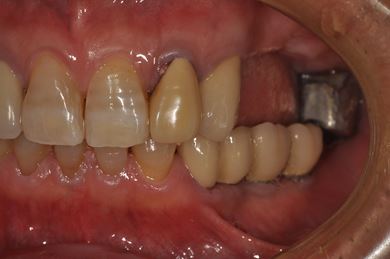

インプラントの症例写真 IMPLANT

骨再生インプラント治療

| 性別/年齢 | 男性 / 58歳 | ||||||||||||||||||||||||||||||||

| 主訴 | ブリッジがだめになったため、現在は部分入れ歯を使用しているが、インプラント治療を検討している。 | ||||||||||||||||||||||||||||||||

| 治療方針 | 左上奥の欠損部分をインプラント治療にて、機能的・審美的回復を行う。 | ||||||||||||||||||||||||||||||||

| 治療内容 | インプラント3本(GBR)、ハイブリッドセラミッククラウン3本 | ||||||||||||||||||||||||||||||||

| 総治療費 | 791,520円 | ||||||||||||||||||||||||||||||||

| 治療期間 | 10ヶ月 |